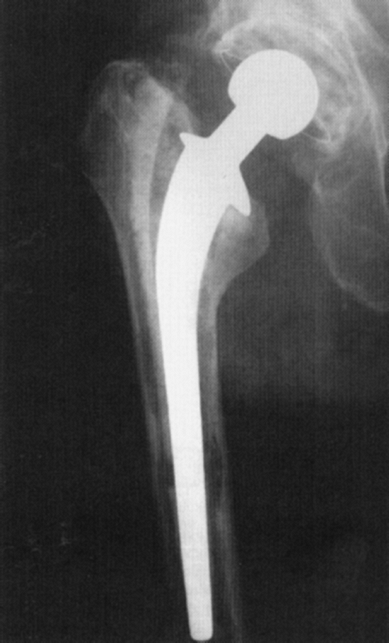

either the femoral or acetabular components is a common cause of

failure of the prosthetic hip. Radiographic changes can be subtle and

often

require the evaluation of serial radiographs taken over a period of

time. Different mechanisms and patterns of failure exist for loosening

of cemented and uncemented prosthesis. Table 2-1 lists the common radiographic findings of aseptic loosening of a total hip arthroplasty.

![]() |

|

Figure 2-14 Anteroposterior radiograph of the femur demonstrates aseptic loosening of the femoral component.